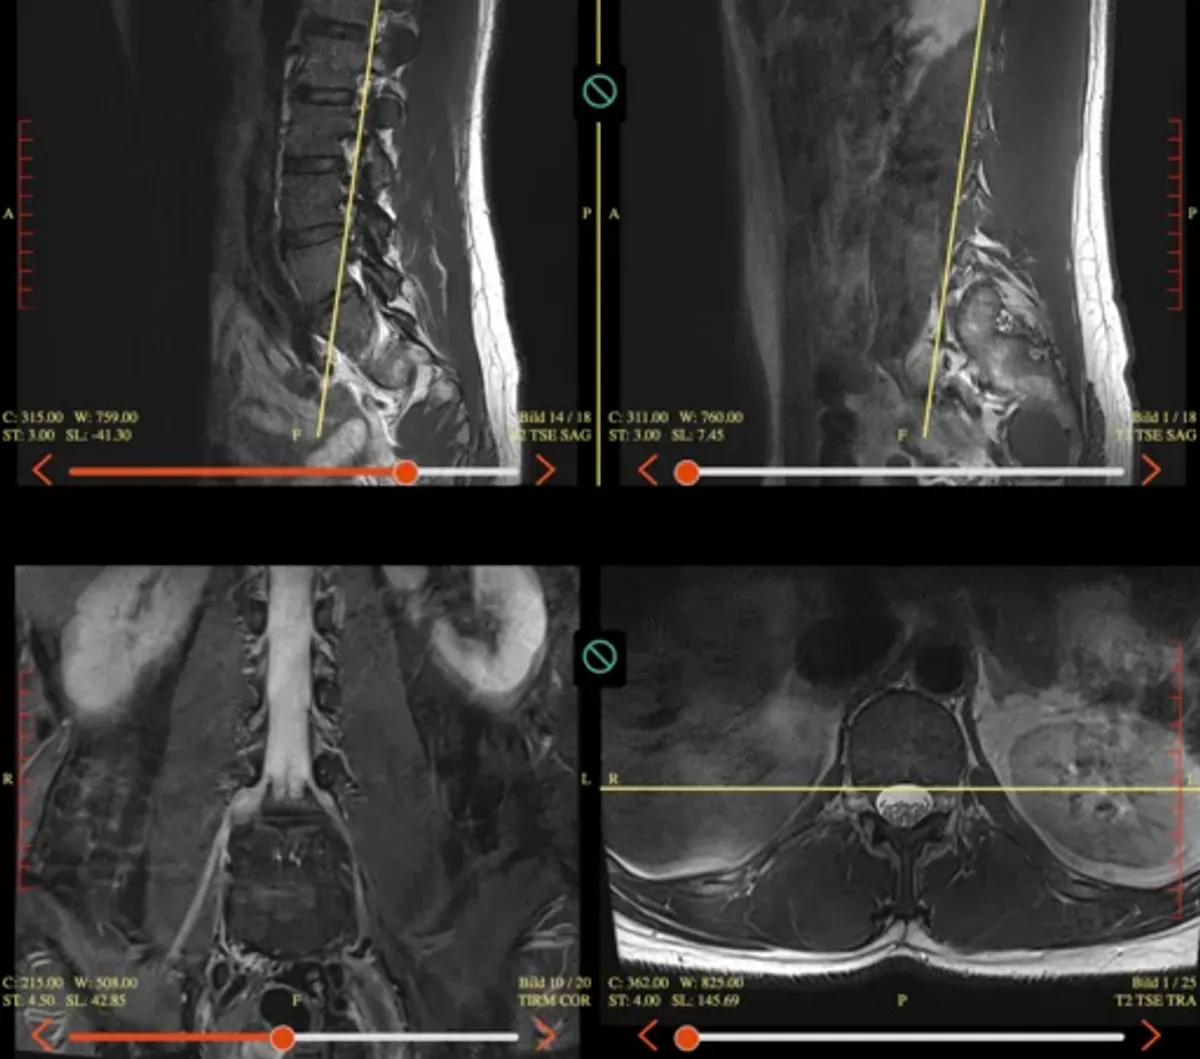

MRI scan that inspired the developer to build a more efficient workout tool

This was my back in 2023. An MRI showed a herniated disc that felt like a death sentence for my training. I had been lifting for years, but suddenly, I was at an absolute low point.